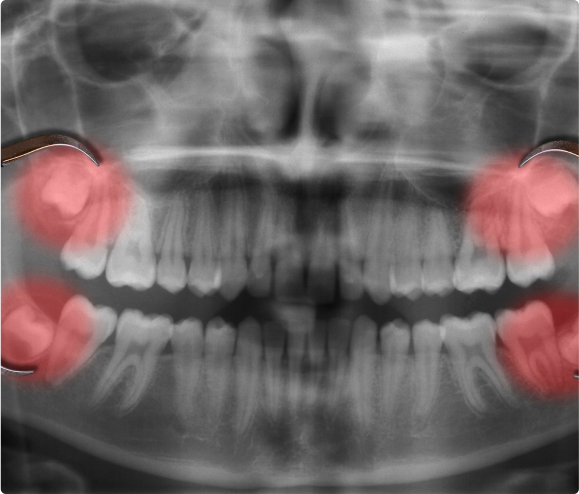

• When they are healthy and properly aligned, wisdom teeth can be a valuable asset to the mouth. However, more often than not, they become misaligned (positioned horizontally, angled toward or away from the second molars, or angled inward or outward) and need to be extracted. Even worse, they can crowd or damage adjacent teeth, the jawbone, or nerves.

• Wisdom teeth also can be impacted, which means they become enclosed within the soft tissue and/or the jawbone or only partially break through or erupt through the gum. Partial eruption of the wisdom teeth allows an opening for bacteria to enter around the tooth and cause an infection, which can cause pain, swelling, jaw stiffness, and general illness. Partially erupted teeth are also more prone to tooth decay and gum disease because their difficult-to-reach location and awkward positioning make brushing and flossing difficult.

• The relative ease with which a dentist or oral surgeon can extract wisdom teeth depends on the position of the teeth and their stage of development. A wisdom tooth that has fully erupted through the gum can be extracted as easily as any other tooth. However, a wisdom tooth that is underneath the gums and embedded in the jawbone will require an incision into the gums and then removal of the portion of bone that lies over the tooth. In such cases, the tooth may be extracted in small sections rather than removed in one piece. This minimizes the amount of bone that needs to be removed to get the tooth out.